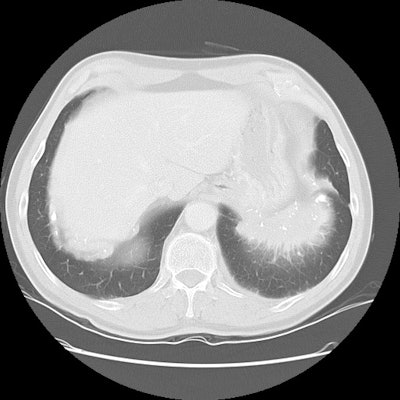

Left SVC: The patient below was incidentally found to have a left SVC (white arrow). Contrast had been injected in the left arm and there was no connection to the right superior vena cava. The left SVC drained to the coronary sinus (black arrows). |